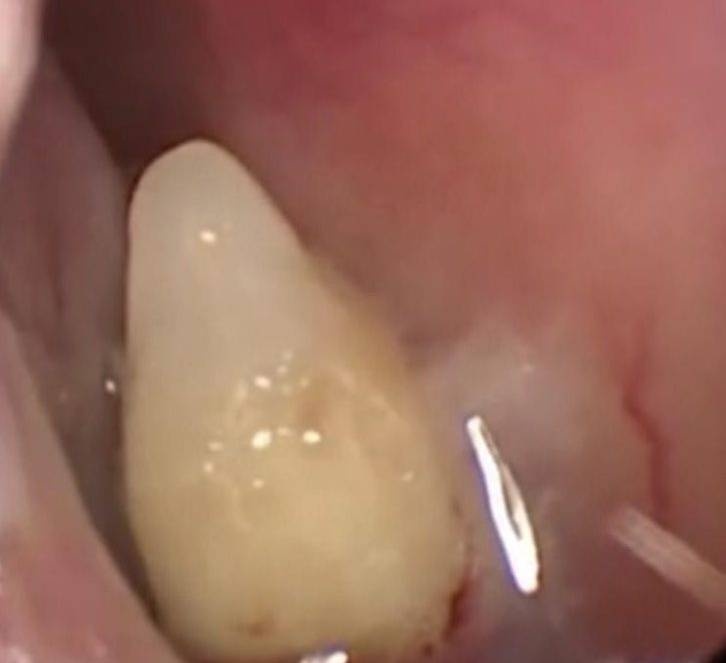

| Chiếc răng mọc trong mũi bà Xia. Ảnh: Asiawire. |

Sau khi phẫu thuật, các bác sĩ lấy ra một chiếc răng đã phát triển đầy đủ.

Theo bác sĩ Zhou Zianpo, hiện tượng răng mọc như trên gọi là răng thừa. Người mắc phải chứng này khiến cho răng mọc ở một vị trí nào đó trên mặt từ khi sinh ra, chúng phát triển lúc còn ở trong bụng mẹ.